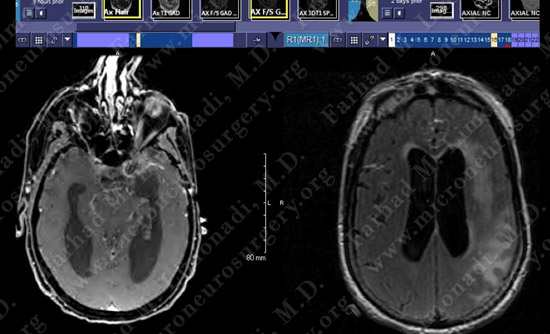

Post-op Imaging

Before Operation After Operation

Post-op day 1 MRI shows complete resection of the tumor with no injury to surrounding neurovascular structures.

At 6 months post-op patient was doing well and his team had won a competitive cognitive game. MRI shows no evidence of recurrence of the tumor by this time.